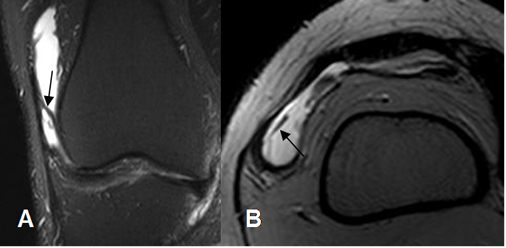

Fig 159. Plica medial.

A y B: RM axial en T2. Imágenes hipodensas en la parte medial de la cavidad articular,

por plicas mediales. En B hay subluxación lateral de la patela.